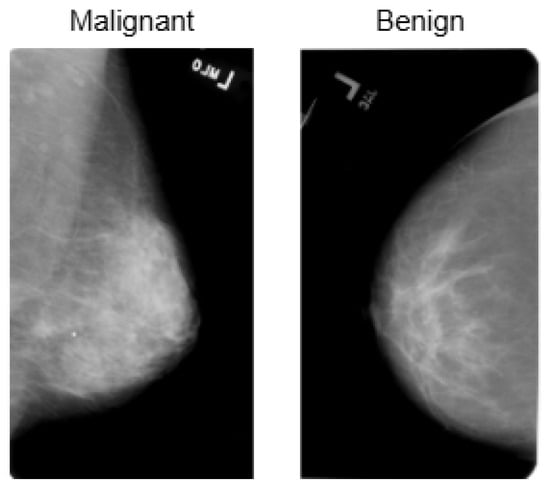

The INbreast dataset consists of 7632 full-field digital mammography (FFDM) images collected from 115 patients. Each image has been meticulously annotated by radiology experts to ensure high diagnostic accuracy. The dataset includes standard mammographic views—craniocaudal (CC) and mediolateral oblique (MLO)—for both breasts, although, in cases of mastectomy, only the remaining side is imaged. This dataset captures a variety of clinical scenarios, including screening, diagnostic, and follow-up procedures. For classification purposes, images are labeled as either benign or malignant. Benign cases encompass cysts, fibroadenomas, and calcifications, while malignant cases include tumors and suspicious lesions. What sets INbreast apart is its high-resolution imaging, acquired using a MammoNovation Siemens FFDM system with solid-state amorphous selenium detectors. The images are stored in DICOM format, featuring a resolution of 70 microns per pixel, with dimensions of either 3328 × 4084 or 2560 × 3328 pixels, depending on the compression plate used. Each image is accompanied by detailed XML-based annotations that provide information on lesion contours, types, biopsy results, and BI-RADS categories (3–6). Furthermore, the dataset includes patient metadata such as age, family history, BI-RADS assessments, and breast density classifications according to ACR standards. Figure 4 illustrates representative samples.

For BreakHis, extensive geometric (rotation ± 20°, flips) and photometric (zoom, brightness) transformations were applied to reflect slide orientation variability and staining inconsistencies. BUSI employed elastic deformation, speckle noise, and contrast adjustment to mimic tissue distortion and signal artifacts. INbreast received conservative adjustments to enhance tissue visibility without losing diagnostic fidelity. CBIS-DDSM used mild rotation, flipping, and brightness changes, maintaining lesion structure integrity. The Combined Dataset integrated harmonized augmentations from all sources, ensuring cross-modality consistency while retaining BUSI-specific elastic transformation. The chosen values prioritize generalization while preventing excessive transformations that could alter pathological features or diminish diagnostic relevance. Figure 6, Figure 7, Figure 8 and Figure 9 illustrate sample images from each dataset after the application of these data augmentation techniques.